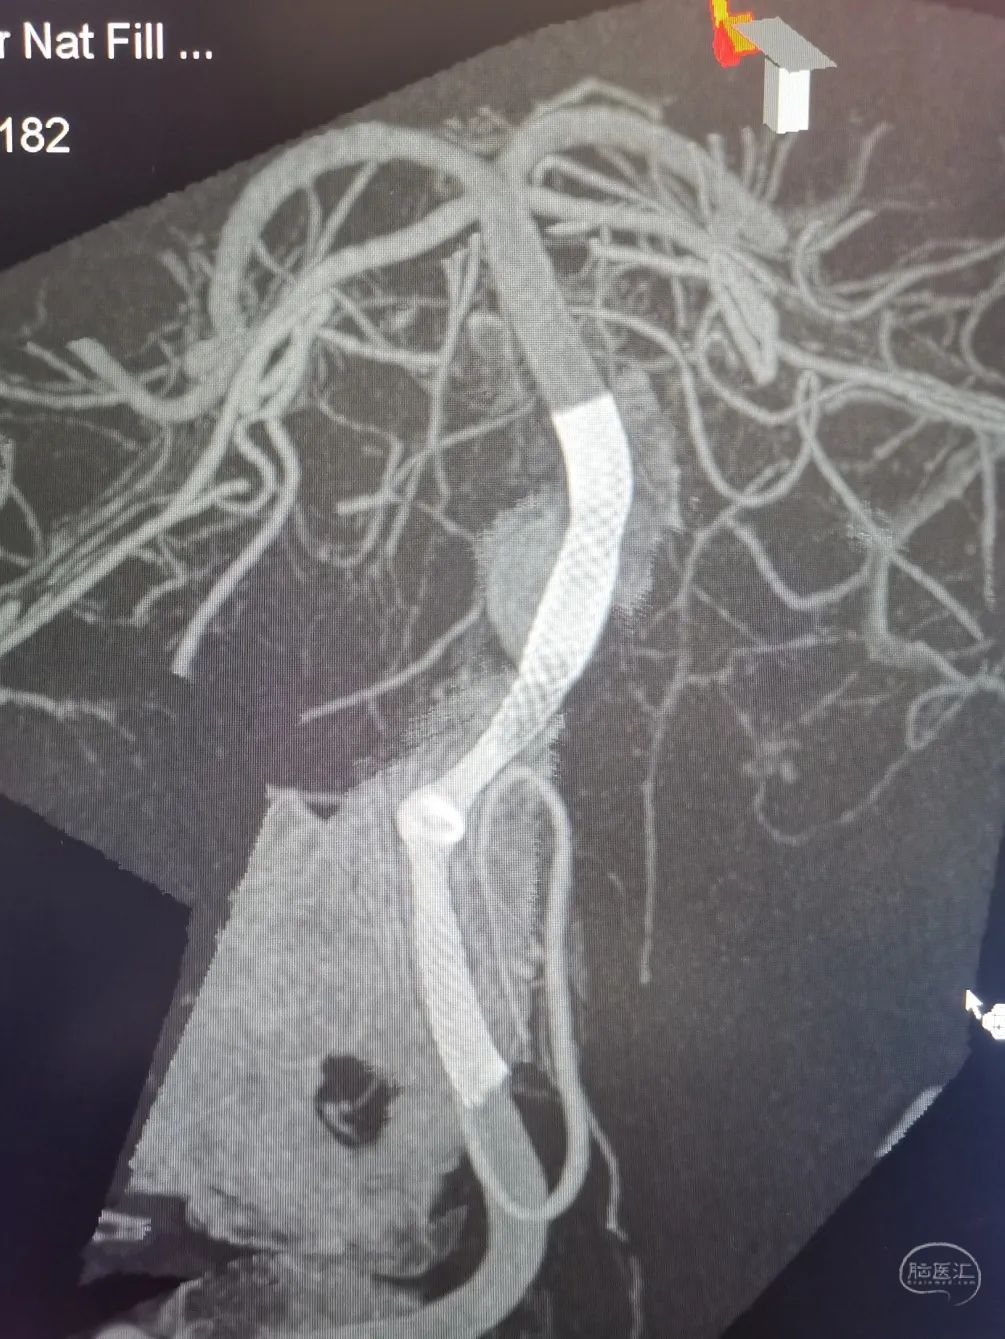

3D重建显示基底动脉下部、双椎结合部、左椎多发夹层动脉瘤:

双抗5天后行左侧椎动脉多发夹层动脉瘤Pipeline™ Flex 血流导向密网支架植入术。

Pipeline™ Flex 血流导向密网支架 PED-325-35

将Phenom™ 27微导管超选进入左侧大脑后动脉内,释放一枚3.25×35mm Pipeline™ Flex血流导向密网支架,远端定位在动脉瘤以远7mm,在动脉瘤处推密,近端定位在PICA起始部上端或远端,支架打开顺利。导引导管内推注替罗非班12mL,支架导管及微导管常规按摩,促进支架贴壁。

术后造影显示动脉瘤内造影剂滞留明显,载瘤动脉通畅。

支架CT: